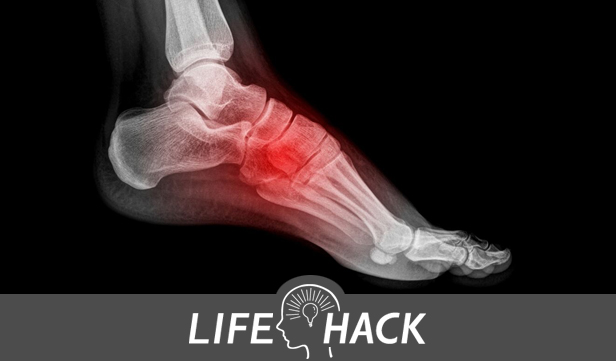

ではその症状は? 自分の場合は左足の甲だったのですが、ずばり「骨折の痛み」そのもの。 朝起きると足が赤黒くパンパンに腫れ上がり、血管が破裂しそうなほど浮き出ている。のたうち回るほど痛くてまったく動けない。20代の頃に同じ箇所を骨折したことがあったので、疲労骨折でもしたのかと救急病院(日曜だった…)でレントゲンを撮っても異常なし。翌日、尿酸値を計ってもらうと9.4という地獄の数値(7を超えると異常らしい)。1週間ほど松葉杖での生活を余儀なくされました。